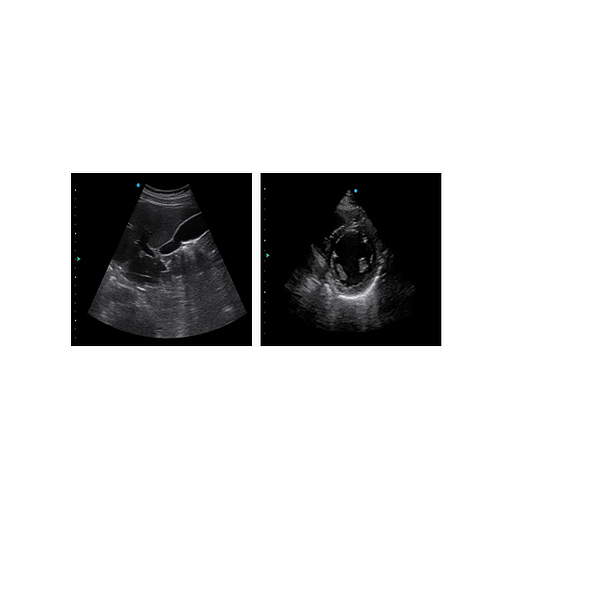

Stress Echo: Hồi âm căng thẳng được sử dụng để chẩn đoán bệnh tim mạch vành, đánh giá chức năng dự trữ mạch vành và thiếu máu cục bộ cơ tim, ước tính khả năng sống của cơ tim, cung cấp thông tin chẩn đoán có giá trị cho PCI & CABG.TDI có thể thu được thông tin về vận tốc, hướng và thời gian của cơ tim để phân tích chức năng tim một cách trực quan hơn. TDI cho phép bạn đánh giá định lượng chuyển động cơ tim cục bộ, quan sát vận tốc cơ tim của các phần tim khác nhau và ước tính xem có tổn thương cục bộ hay không, cũng như đánh giá chức năng tâm trương sớm.Vis-Needle: Bằng cách nhấn mạnh hình ảnh của kim, nó làm tăng độ an toàn và độ chính xác của quy trình sinh thiết và các quy trình can thiệp khác bao gồm các khối thần kinh và đường vào mạch máu.

4D Pro (Có sẵn) Công cụ hình ảnh 4D mới, cho hình ảnh sống động như thật và sự tin cậy trong chẩn đoán.